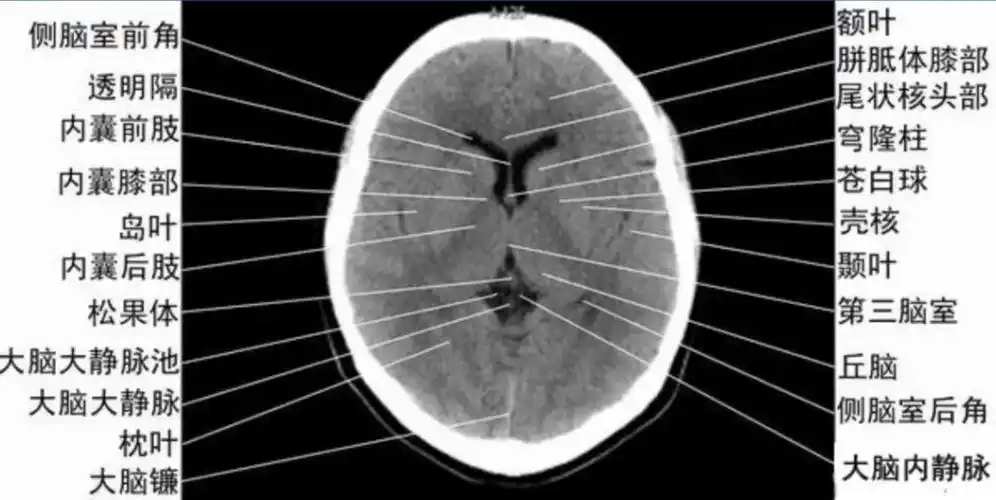

颅脑ct的正常解剖

影像医生必须掌握的头颅ct解剖与常见出血梗死判读

解剖入门颅脑ct断层中英文对照

详细标注版——颅脑ct正常解剖图谱_中央_小脑_纤维